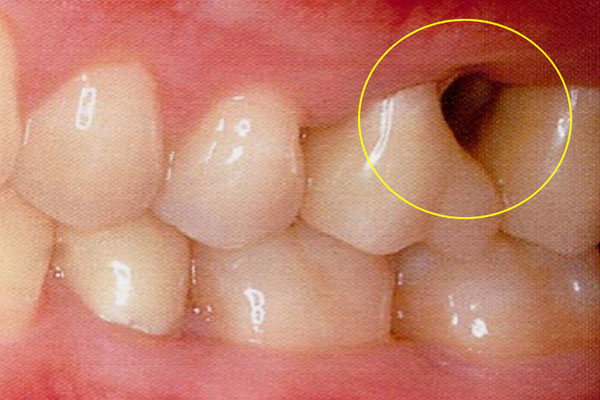

歯周病が進行して、歯の根元まで炎症が広がることがあります。右の写真をご覧ください。赤丸で囲んだ分が黒くなっています。ここは、歯肉が衰え、歯と歯肉の間にできたすき間です。ここに付着した歯石を取り除くことはできません。放置すると歯周病がさらに進行して、やがて抜歯となってしまうでしょう。

そこで、外科的手術で歯の根を露出させて歯石を取り除きます。さらに歯の根の間に歯間ブラシが入るように穴をあけ、お手入れしやすくします。この術式を「トンネリング」といいます。